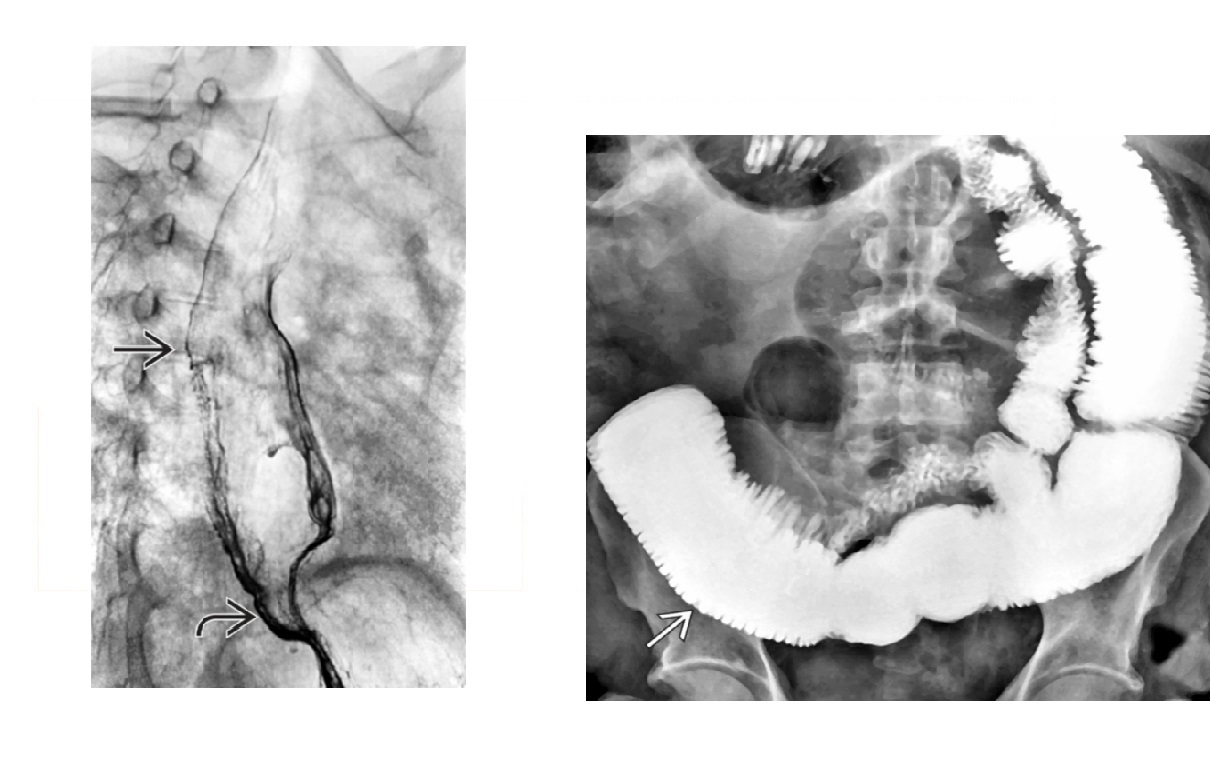

HHT **Tortuous and prominent hepatic arterial branches ** Dilated hepatic veins and early filling Arterial phase, mosaic attenuation of the liver with multiple enhancing foci aka Osler-Weber-Rendu syndrome Hereditary multiorgan disorder → fibrovascular dysplasia with development of telangiectasias and arteriovenous malformations (AVMs)